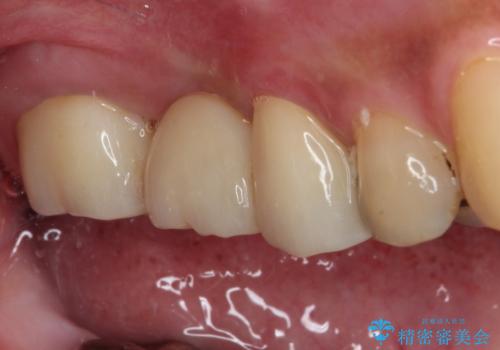

虫歯が大きく進行していましたが、歯髄(神経組織)にまで及ぶものではなかったため、無事に虫歯治療を行うことができました。

歯石もしっかりと除去したことで、周辺の腫れていた歯肉も引き締まり、健全な状態となりました。